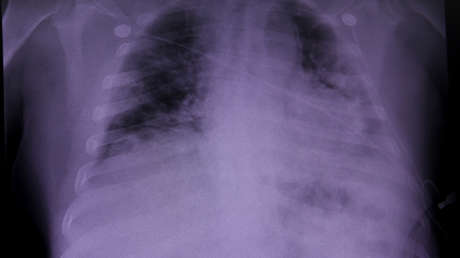

Durante el estudio, que fue publicado este martes en EBioMedicine, los científicos analizaron muestras de tejido pulmonar, hepático y renal de 41 pacientes que fallecieron a causa del coronavirus en el Hospital Universitario de Trieste (Italia) al inicio de la pandemia, entre febrero y abril de 2020.

Tras los análisis, los investigadores identificaron que el 90 % de las personas estudiadas mostraron una extensa coagulación de la sangre de las arterias y venas del pulmón (trombosis), así como la presencia de varias células pulmonares anormalmente grandes y con muchos núcleos, producto de la fusión de diferentes células en una sola célula grande, ambos síntomas característicos del covid-19 en comparación con otras formas de neumonía.

Por su parte, Mauro Giacca, coautor del estudio, apuntó que no se encontraron signos de infección viral o inflamación prolongada en otros órganos, y que identificaron "una destrucción realmente vasta de la arquitectura de los pulmones", en la que el tejido pulmonar sano fue "casi completamente sustituido por el tejido cicatricial".

Asimismo, el investigador señaló que "los hallazgos indican que el covid-19 no es simplemente una enfermedad causada por la muerte de las células infectadas con el virus, sino que es probablemente la consecuencia de que estas células anormales persistan durante largos períodos dentro de los pulmones".

Del mismo modo, los autores descubrieron que la presencia de células infectadas por SARS-CoV-2 es capaz de provocar sensibles cambios estructurales en la anatomía pulmonar, mismos que pueden persistir durante varias semanas o meses y podrían explicar eventualmente el 'covid largo'.